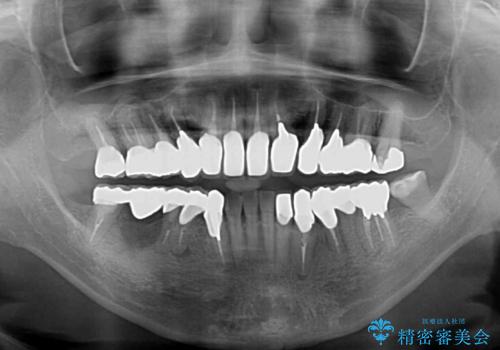

仮歯で咬み合わせの調整を行ってからは、特に不安定になることもなく、非常にスムーズに治療を進めて行くことができました。

前歯奥歯ともに望ましくない力がかかりやすい咬み合わせであるため、就寝時にはマウスピースを使用するようにお伝えしております。